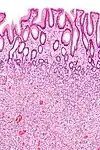

| Type de polype | Apparence histologique | Risque de malignité | Coupe histologique | Syndromes | |

|---|---|---|---|---|---|

| Hyperplasique | Cryptes dentées non-ramifiées | Non |  | Hyperplasique polypose syndrome | |

| Adénome dentelé sessile | Semblable à hyperplasique avec hyperserration, bases des cryptes dilatées/ramifiées, des cellules de mucine apparents à la base des cryptes | Oui |  | ||

| Inflammatoire | Muqueuse/sous-muqueuse élevées avec inflammation | Si développement d'une dysplasie | Maladies inflammatoires chroniques intestinales, ulcères, infections, prolapsus muqueux | ||

| Adénome tubulaire (villositaire, tubulovilleux) | Glandes tubulaires avec des noyaux allongés (au moins à faible teneur atypie) | Oui |  | ||

| Adénome dentelé traditionnel | Cryptes dentelées, souvent une structure villeuse, avec atypie cytologique, des cellules éosinophiles | Oui |  | ||

| Polype de Peutz-Jeghers | Faisceaux musculaires lisses entre l'épithélium non-néoplasique, apparence d'« arbre de Noël » | Non |  | Syndrome de Peutz-Jeghers | |

| Polype juvénile | Glandes kystiques dilatées avec la lamina propria élargie | Non intrinsèquement, peut développer une dysplasie |  | Syndrome de polypose juvénile, polypes identiques que dans le syndrome de Cronkhite-Canada | |

| Polype hamartomateux | Variable ; polype classique légèrement fibreux avec la muqueuse désorganisée et écartement des muscularis mucosae ; aussi inflammatoire, juvénile, lipome, ganglioneurome, lymphoïde | Non | Maladie de Cowden | ||

| Polype fibroïde inflammatoire | Cellules en fuseau avec des amas concentriques de cellules fusiformes autour des vaisseaux sanguins et l'inflammation riche en éosinophiles | Non |  | ||